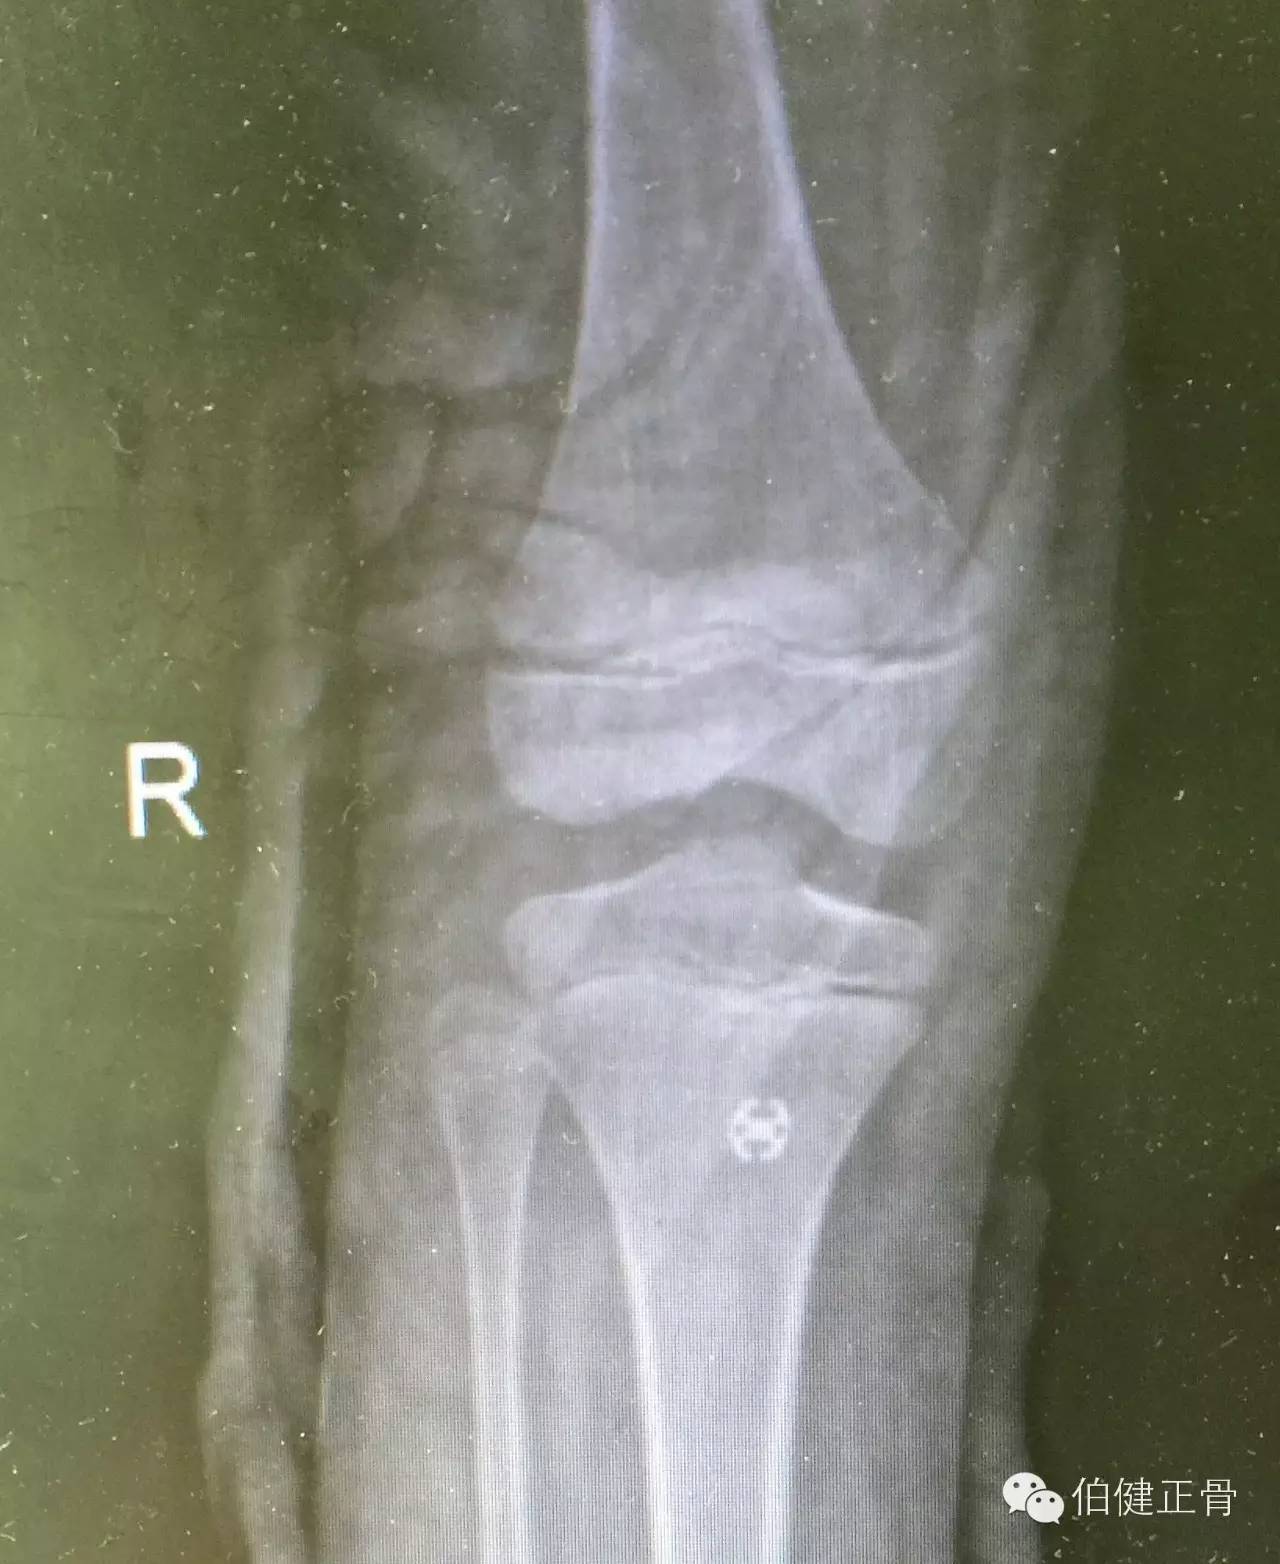

术后复查膝关节正侧位片,骨折解剖复位,完美收工:

正位完全复位: